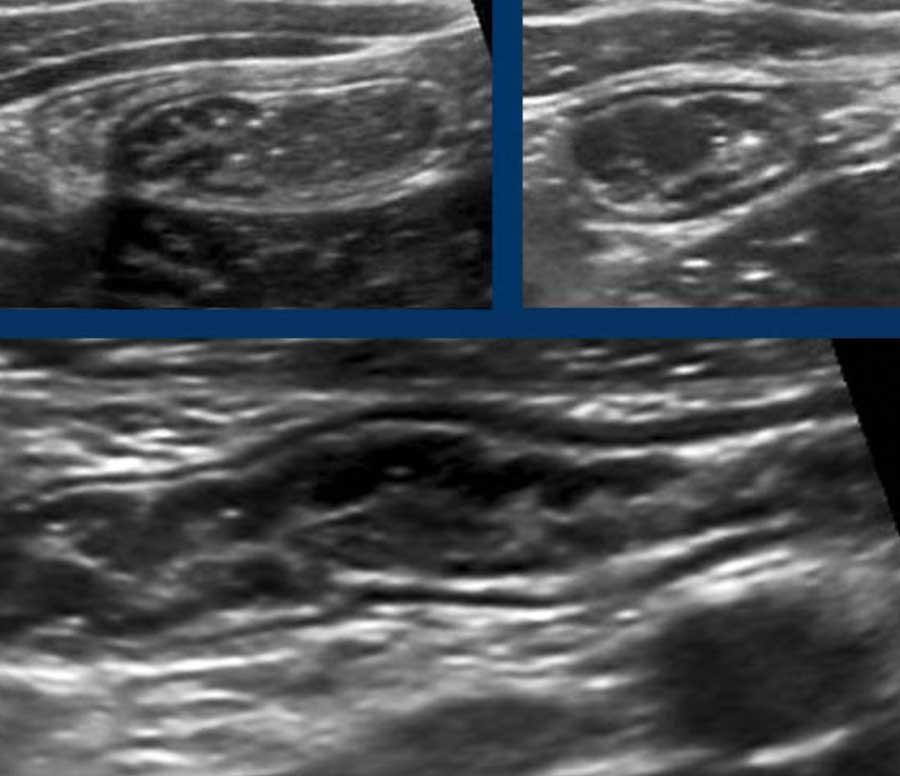

Đây là hình ảnh của hồi tràng tận cùng ở ba trẻ em và người trẻ tuổi khác nhau với các mảng Peyer lớn biểu hiện dưới dạng dày lớp niêm mạc sâu không đối xứng, giảm âm.

Với mỗi kháng nguyên mới, mô bạch huyết lại được tái hoạt hóa.

Ở bệnh nhân trẻ tuổi, cả hạch bạch huyết mạc treo ruột và các mảng Peyer đều lớn hơn nhiều so với người trưởng thành – kể cả về kích thước tuyệt đối.

Mô bạch huyết bị kích thích ở trẻ em không chỉ dẫn đến các mảng Peyer nổi bật ở hồi tràng đoạn cuối và các hạch bạch huyết mạc treo ruột phì đại (hình dưới bên trái), mà còn gây ra tình trạng dày lớp niêm mạc sâu của ruột thừa (hình dưới bên phải).

Lưu ý rằng các phần lồi ra –đôi khi giống polyp- (góc trên bên phải), có thể đóng vai trò là điểm dẫn đầu trong lồng ruột hồi-manh tràng điển hình ở trẻ nhỏ